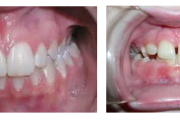

Vali sind huvitav pilt ja me näitame sellega seotud haigust ja sümptomeid